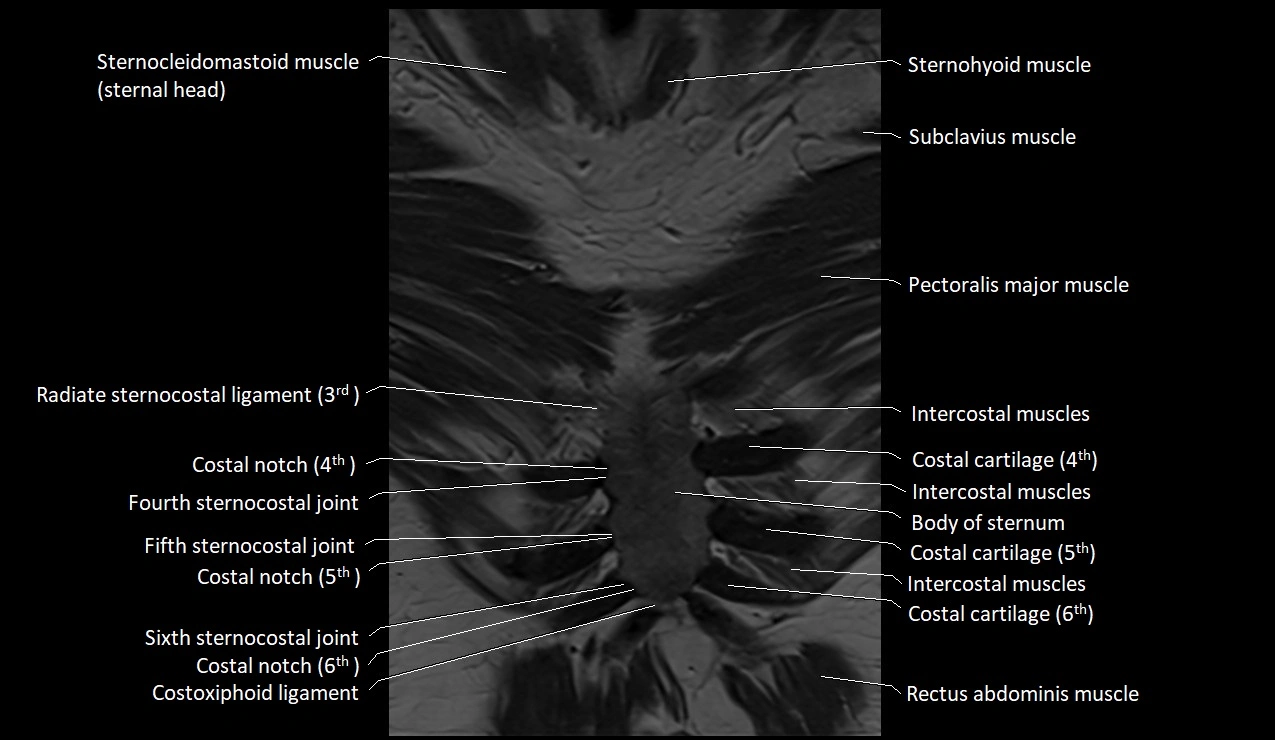

MRI images

image